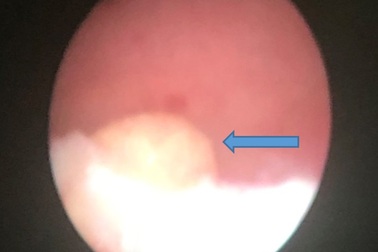

Tự lấy sỏi thận qua đường niệu bằng… cọng cỏBệnh viện An Bình (TP.HCM) vừa ghi nhận một trường hợp hi hữu, bệnh nhân tự lấy dị vật nghi sỏi thận qua đường niệu bằng... cọng cỏ.